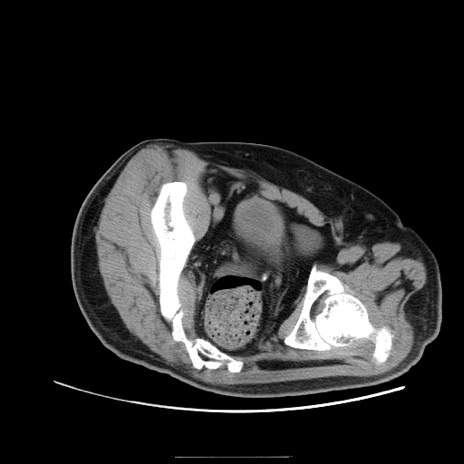

冠状断像

【症例】50歳代男性

【主訴】腹痛

【現病歴】AVMからの被殻出血のため回復期リハ病棟入院中。 本日午後3時頃急に下腹部痛が出現した。

【既往歴】AVM、被殻出血、虫垂炎、高血圧

【身体所見】意識晴明、左半身不全麻痺、会話の理解は良好、36.5°C、腹部:膨隆、全体に板状硬、下腹部正中に圧痛点あり、反跳痛-、筋性防御不明、右下腹部にope scar

【データ】WBC 9400、CRP 0.06